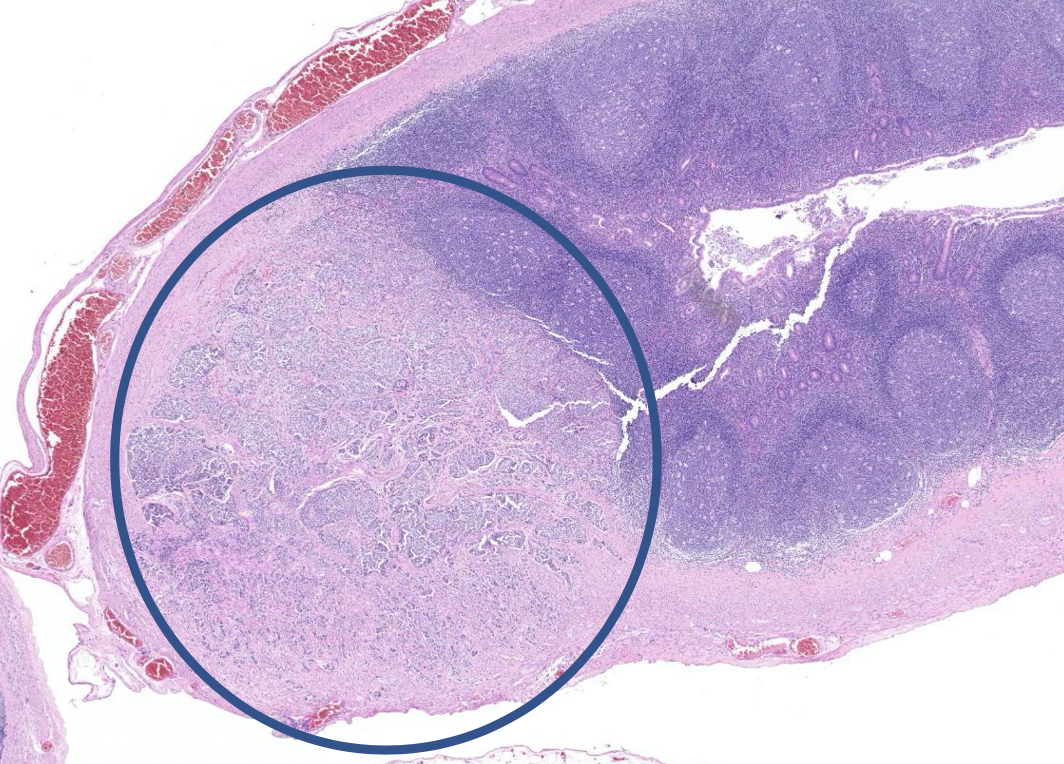

Diagnose?

Hyperplastischer Colonpolyp